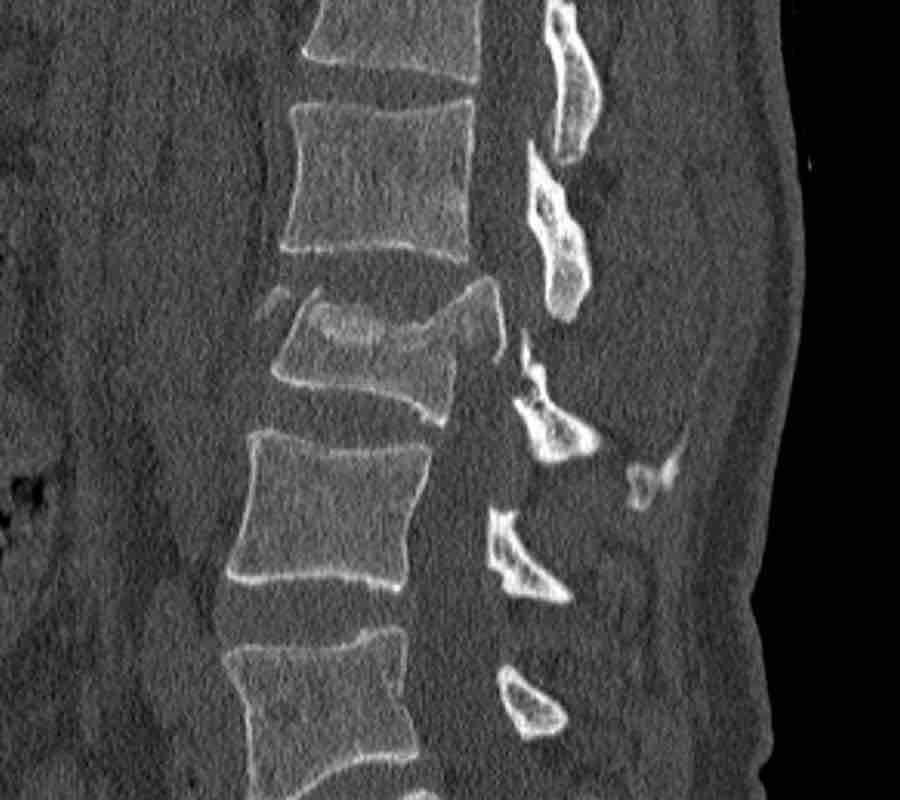

Here more examples of typical burst injuries.

Due to the axial force, the vertebral body is ‘split in half’, therefore a sagittal course of the fracture is common.

Therefore a fracture through the posterior osseous structures is possible in some type A injuries and should not always be regarded as a posterior distraction injury.

This can be confusing sometimes.